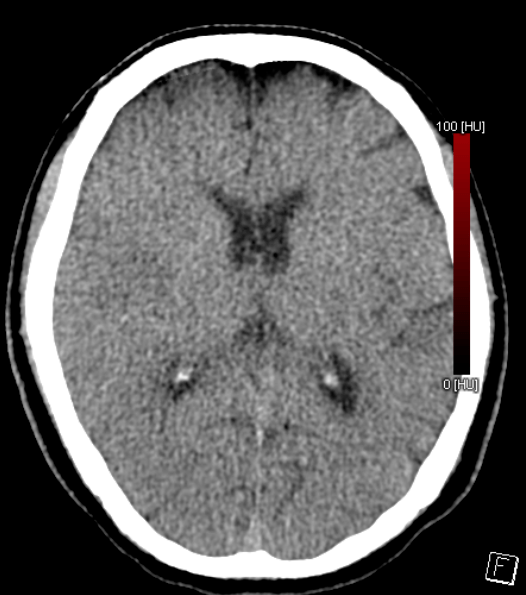

巴氏征阳性图

对光反射消失,左侧 直径3mm,对光反射存在,双侧球结膜水 肿,颈强阳性

对光反射无,示齿伸舌不配合,四肢肌力无法查,肌张力高,双侧巴氏征阳性